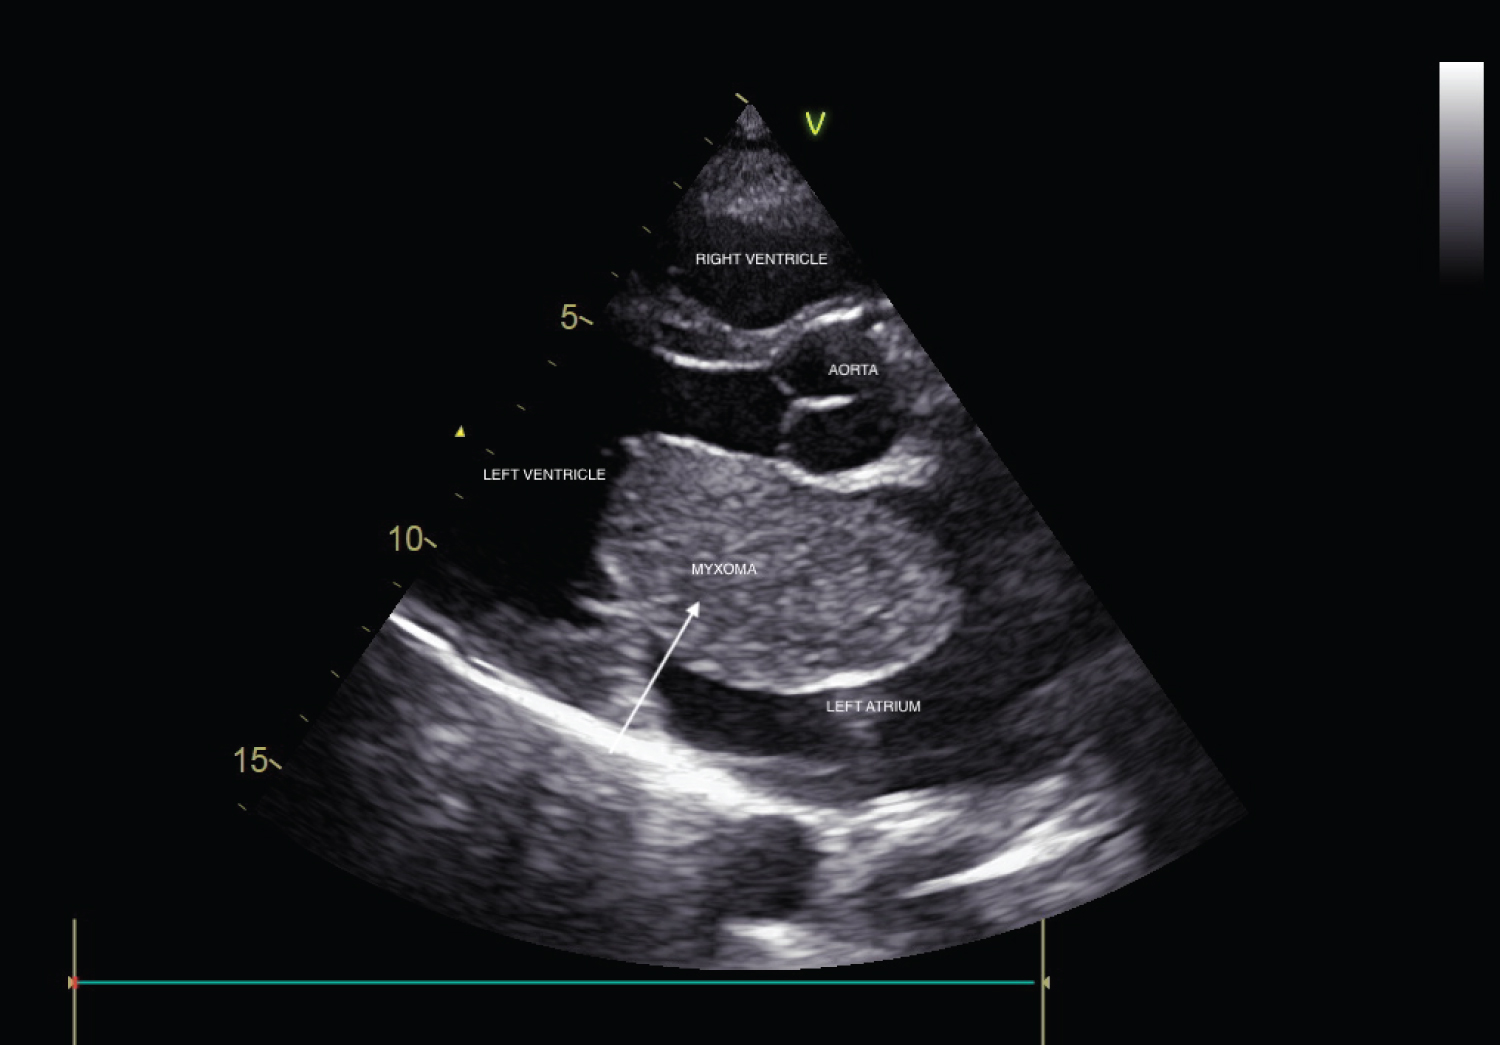

A 45-year-old male was referred to the out-patient clinic of Cardiology department with complaints of recurrent lightheadedness and dizziness on standing and changing postures in bed for past 3 months. He was normotensive, and non-diabetic person with no history of chest pain, dyspnea, palpitations, TIA or stroke. His ECG was unremarkable. CVS examination revealed a low pitch, early diastolic sound along with a soft systolic murmur at the apex. 2D-Echocardiographic study revealed a large, pedunculated mass in the left atrium with stalk attached to fossa ovalis region (Figure 1, Figure 3, Video 1 and Video 2). M-mode echocardiography showed a mass 'plopping' out through LA producing a characteristic multiple diastolic echoes within the mitral orifice as well as systolic echoes within the left atrium (Figure 2). Patient underwent emergency operation for resection of LA mass (Figure 4). Histopathological findings were consistent with myxoma. There was no recurrence of myxoma 6 months post-excision.

Figure 1: Parasternal long axis view on two-dimensional echocardiography showing large mass inside left atrium.